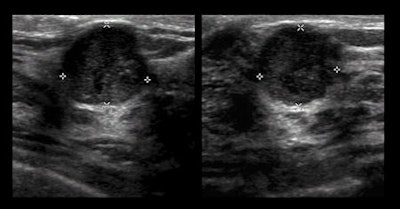

Ultrasound's benefit

There were 32 cancers (29%) that were discovered by ultrasound alone, while nine cancers (8%) were found exclusively by MRI after both mammography and ultrasound failed to detect the abnormalities. A total of 11 cancers (10%) were not detected by any of the three imaging modalities, including nine cancers (8%) detected clinically in the interval between screenings.

Supplemental ultrasound also increased cancer detection with each screening beyond mammography by uncovering an additional 5.3 cancers per 1,000 women in the first year and 3.7 more cancer cases per 1,000 per year in each of the second and third years of screening. Sensitivity for mammography plus ultrasound was 76%, specificity was 84%, and positive predictive value of biopsy was 16%.